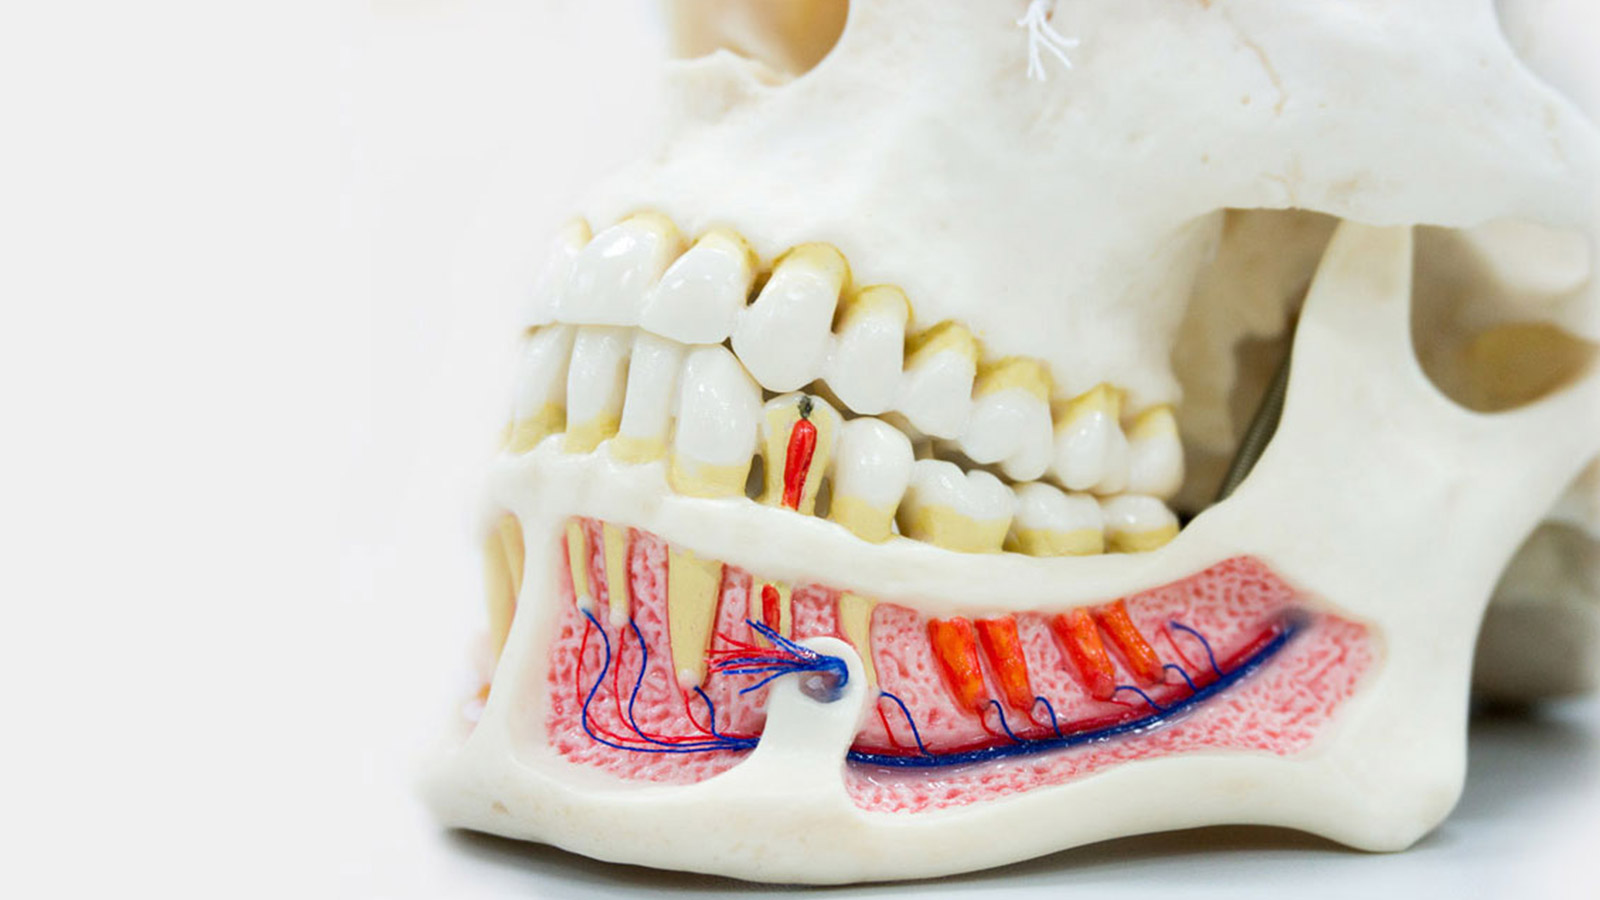

ORALCHIRURGIE

Die Diagnostik und die chirugische Behandlung von Unregelmäßigkeiten und pathologischen Veränderungen der Zähne, den Weichteilen und Knochenstrukturen der orofazialen Region.

DIE DIGITALE UND 3D RADIOGRAPHIE

Die genauste Technologie, mit der wir die Einzelheiten der Zahnkronen, Wurzeln, Paradontium, Alveolarknochen und die anderen Änderungen sehen können.

PARODONTOLOGIE

Behandlung von Stützstrukturen der Zähne, einschließlich Zahnfleisch, Knochen und Desmodont. Die Kürretage und die Verarbeitung der Parodontaltaschen, Parodontalchirurgie, Gingivektomie, Frenektomie.

ENDODONTIE

Maschinenendodontie als perfekteste Therapiemethode für pathologische Prozesse in der Zahnpulpa.